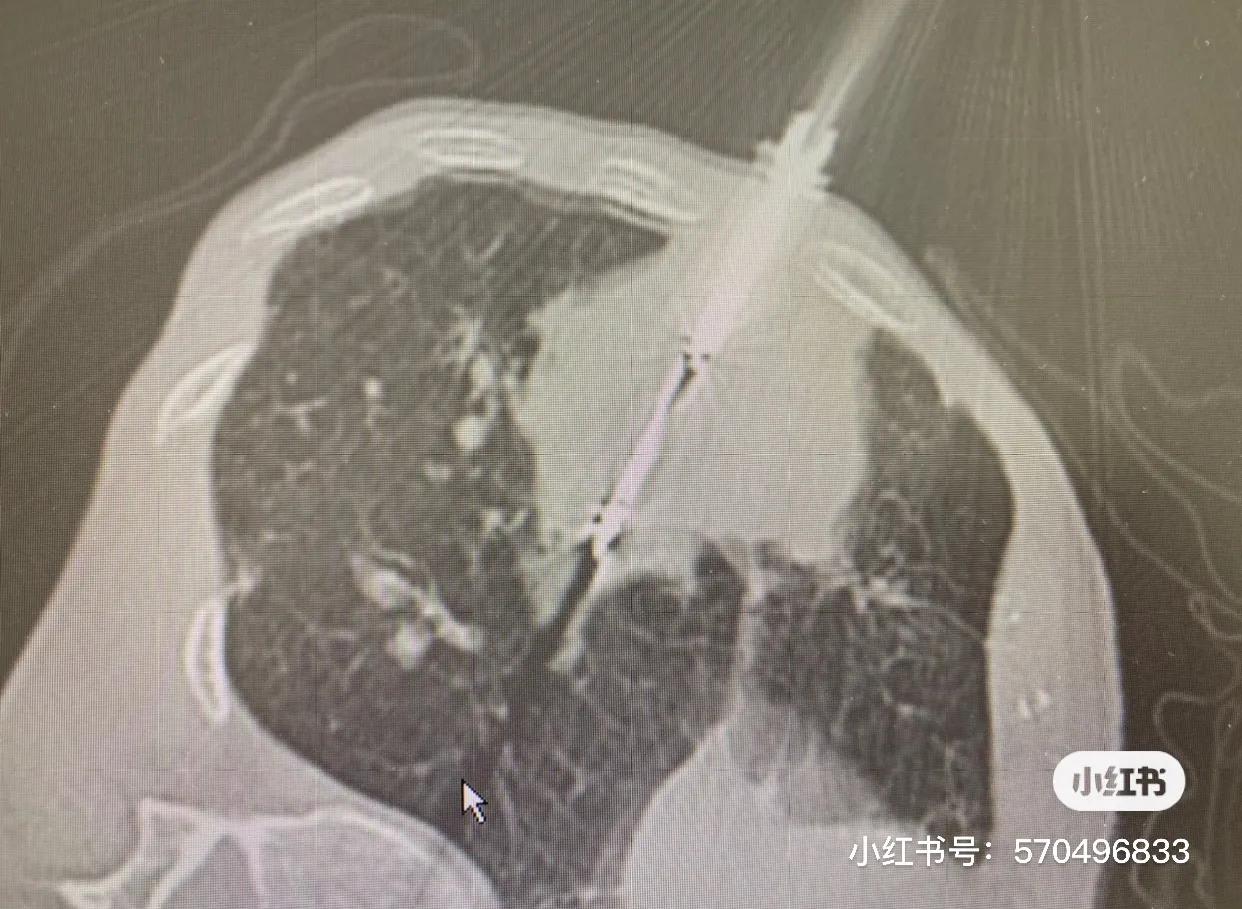

第一次冷冻前CT